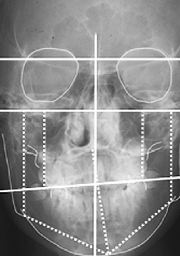

Eruption Charts: Not As Scary As They Sound